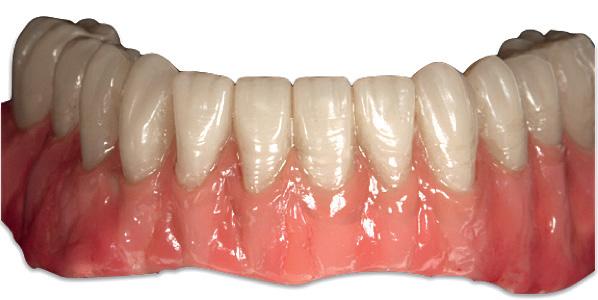

A combination of a rigid metal structure over the telescopic bar and a thimble structure made of PEEK (Fig. 13,14) works as base for the final restorations.

In this case, a patient presented with extremely atrophic bone in the mandible, with four short implants placed between the dental nerve foramen (Fig, 10a,10b). These were milled out of a BRILLIANT Crios disc either as single tooth units or bridges and cemented on the thimble struc-ture (Fig. 15-17). Using BRILLIANT Crios instead of prefabricated teeth, we can increase the strength of the restoration, have good aesthetics and keep the weight low for this kind of prosthesis.

Fig. 17: BRILLIANT Crios restorations used for removable telescopic implant prosthesis.

Fig. 18: Final case in the mouth of the patient. Wearing a complete denture on top and tele-scopic BRILLIANT Crios on the